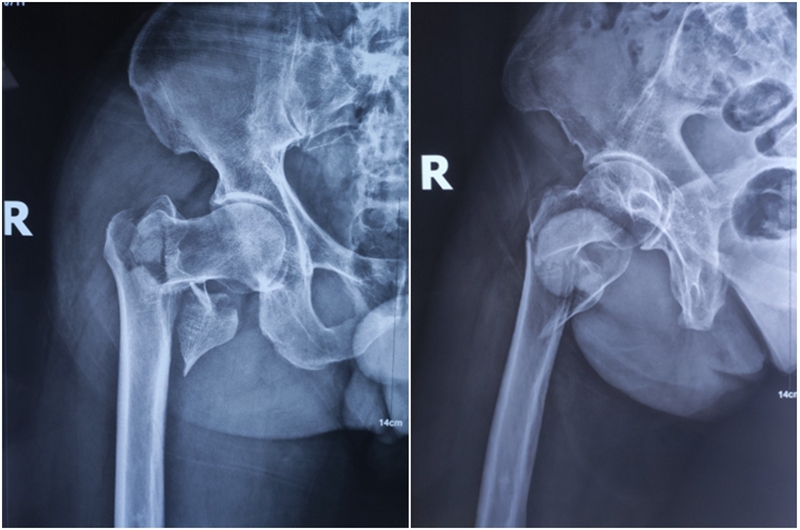

图1 典型病例xx男71岁粗隆间骨折3天Evans-Jensen分型V型4骨折片段,缺乏内侧和外侧的支持

Xxx,男,71岁,右股粗隆间骨折3天,Evans-Jensen分型V型4分骨折块骨折;2020.2.28手术。

图18、图19